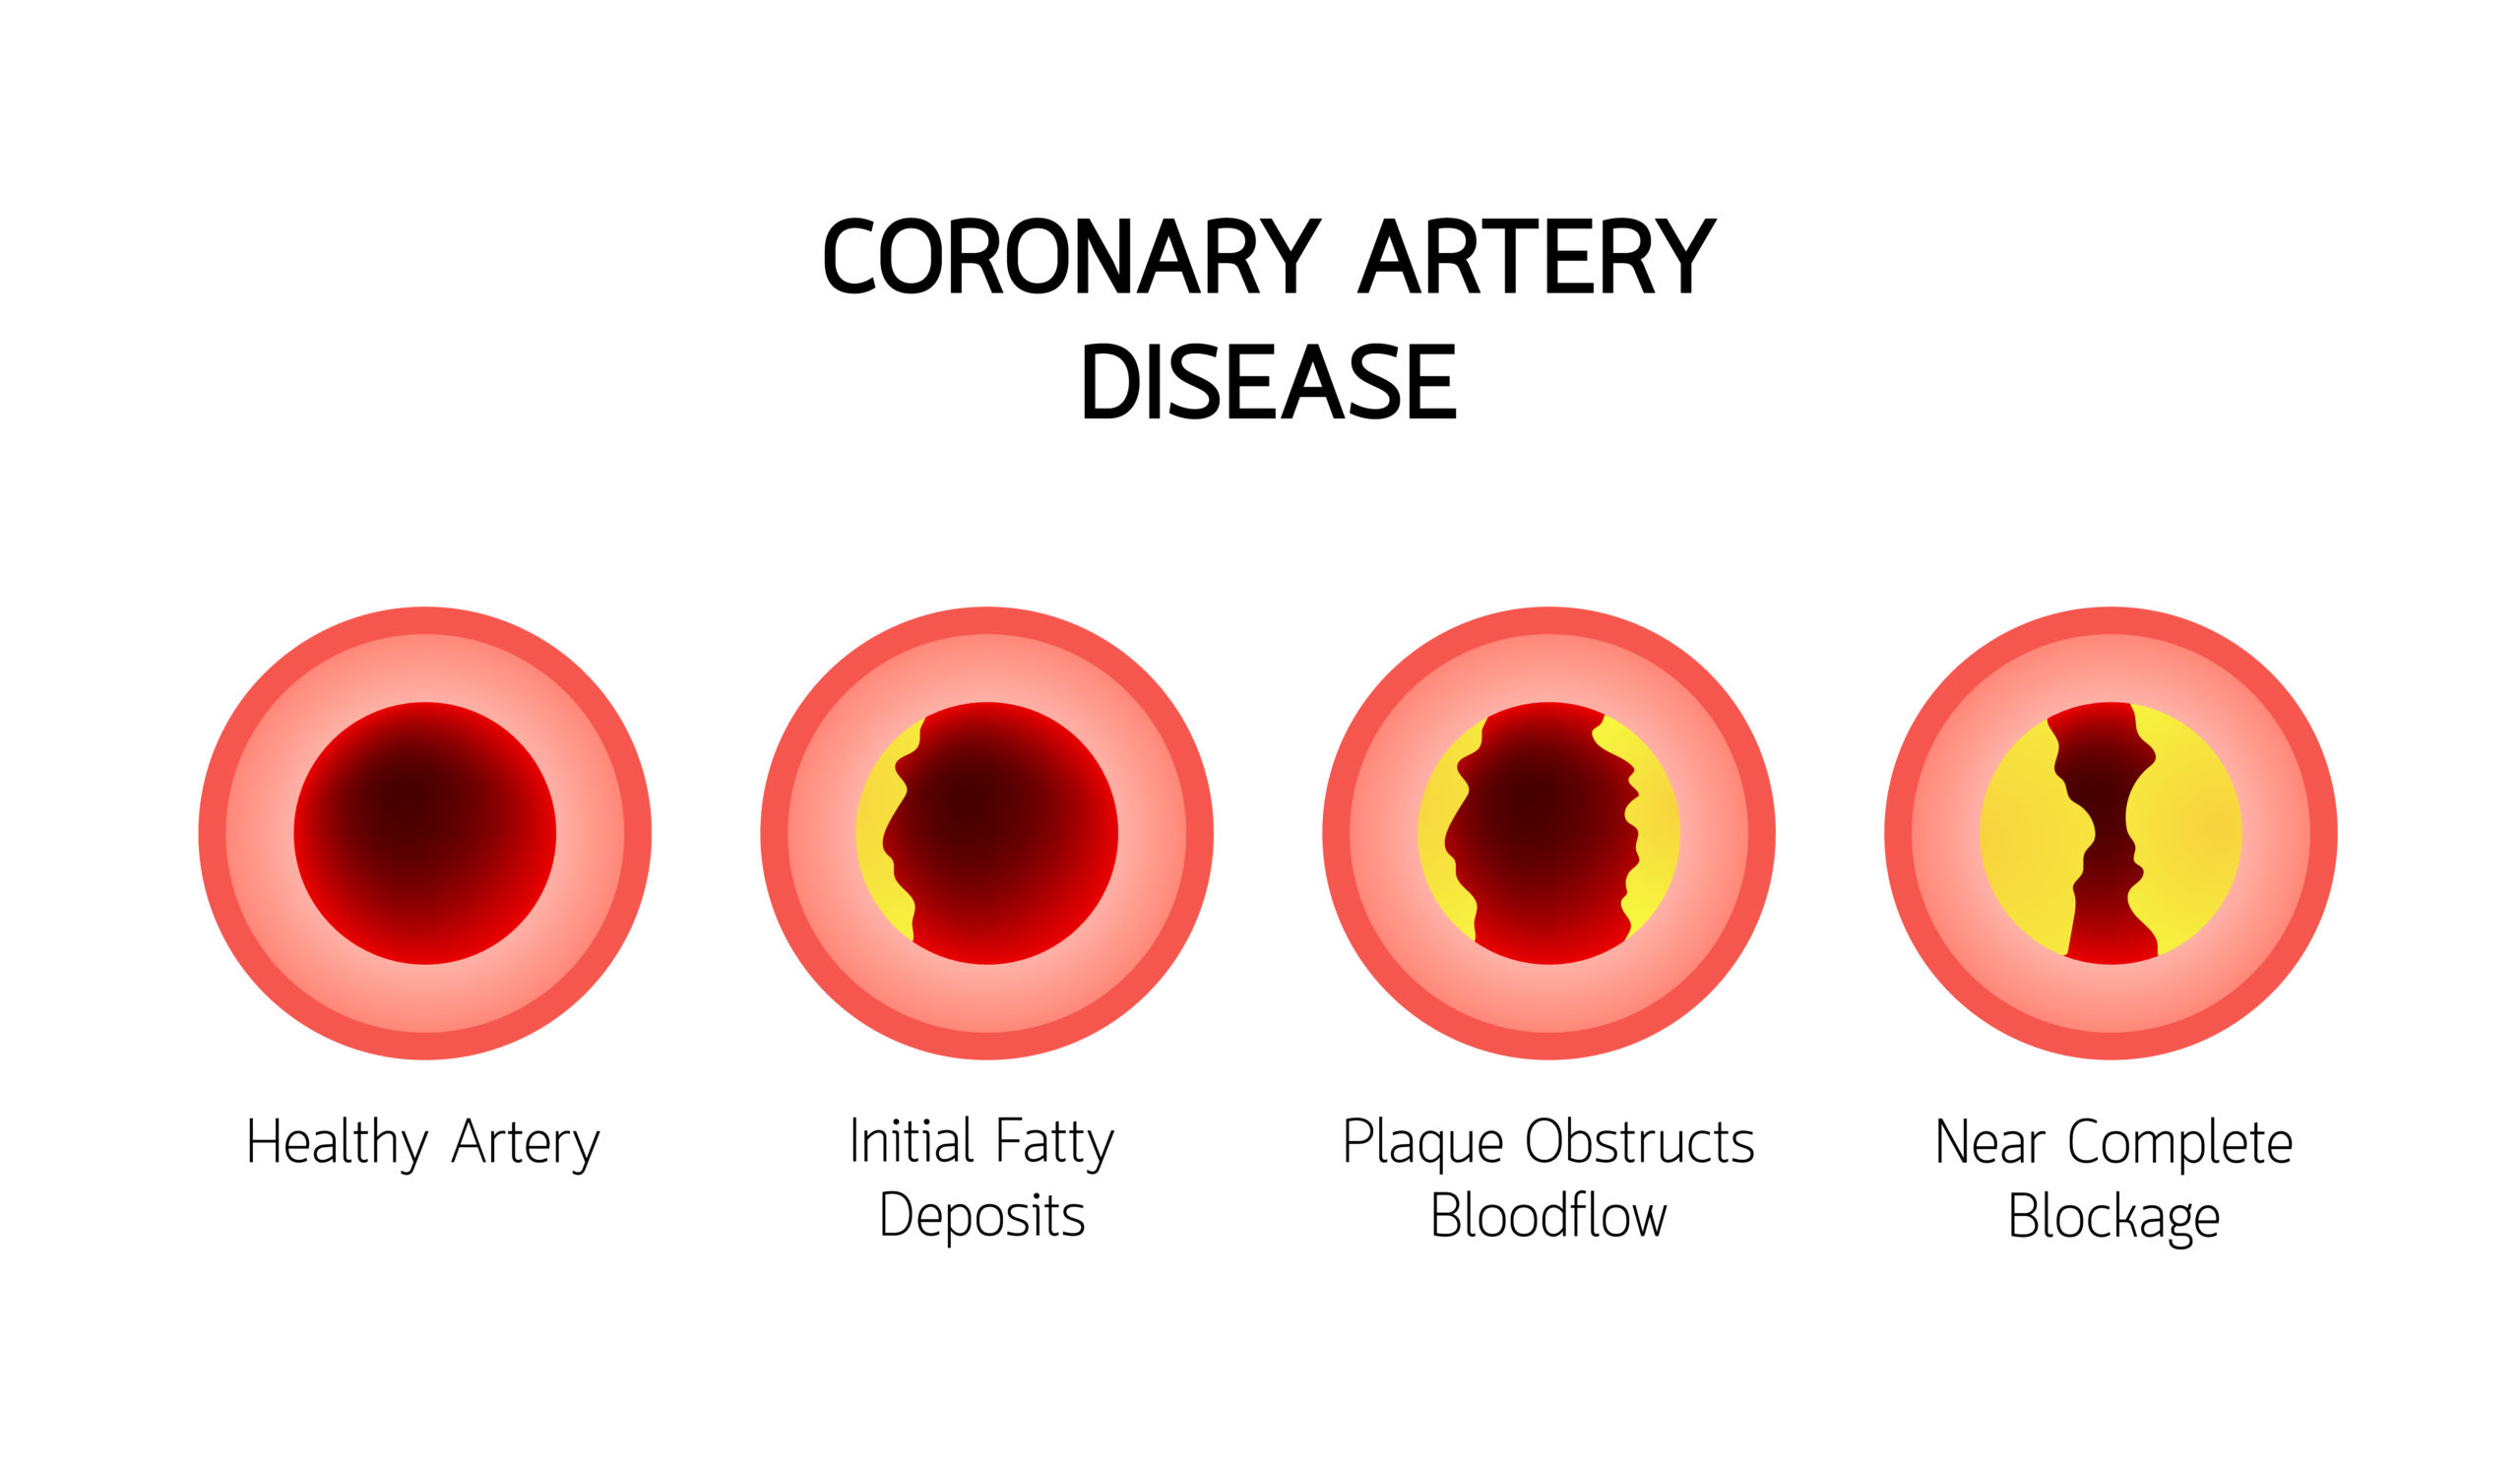

coronary artery disease

A pooled analysis of randomized trials found that moderate to severe coronary artery calcification (CAC) is associated ...

Coronary computed tomography angiography (CCTA) can detect atherosclerosis, even among individuals with no coronary ...